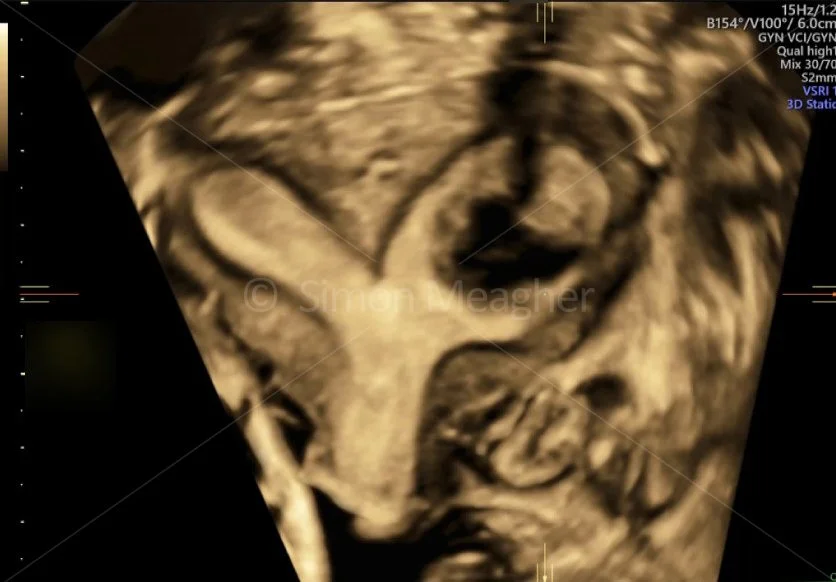

Subseptate Uterus

Uterus